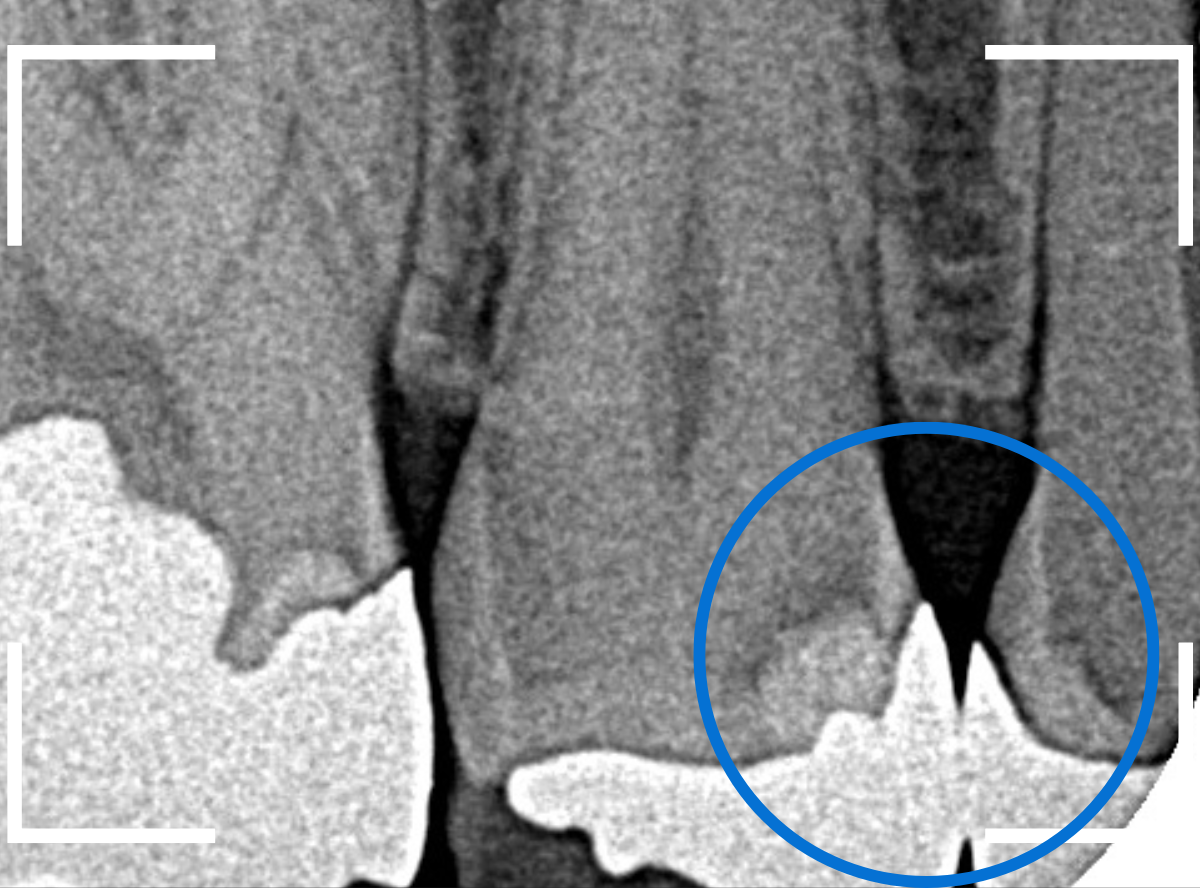

Case.14 インレーの下の歯肉まで広がった虫歯

「下の奥歯が噛むと痛む」という症状で来院された患者さんのケースです。

お口の中の状態を確認すると、奥歯の端に穴が開いているのが見えます。

ここかな?

レントゲン写真で確認します。

やはり、奥歯の端が大きな虫歯になっています。

青いラインが歯の神経、赤いラインが虫歯です。

レントゲン写真上では虫歯が神経まで達しているように見えます。

これは、神経を取らないとダメかもしれません。